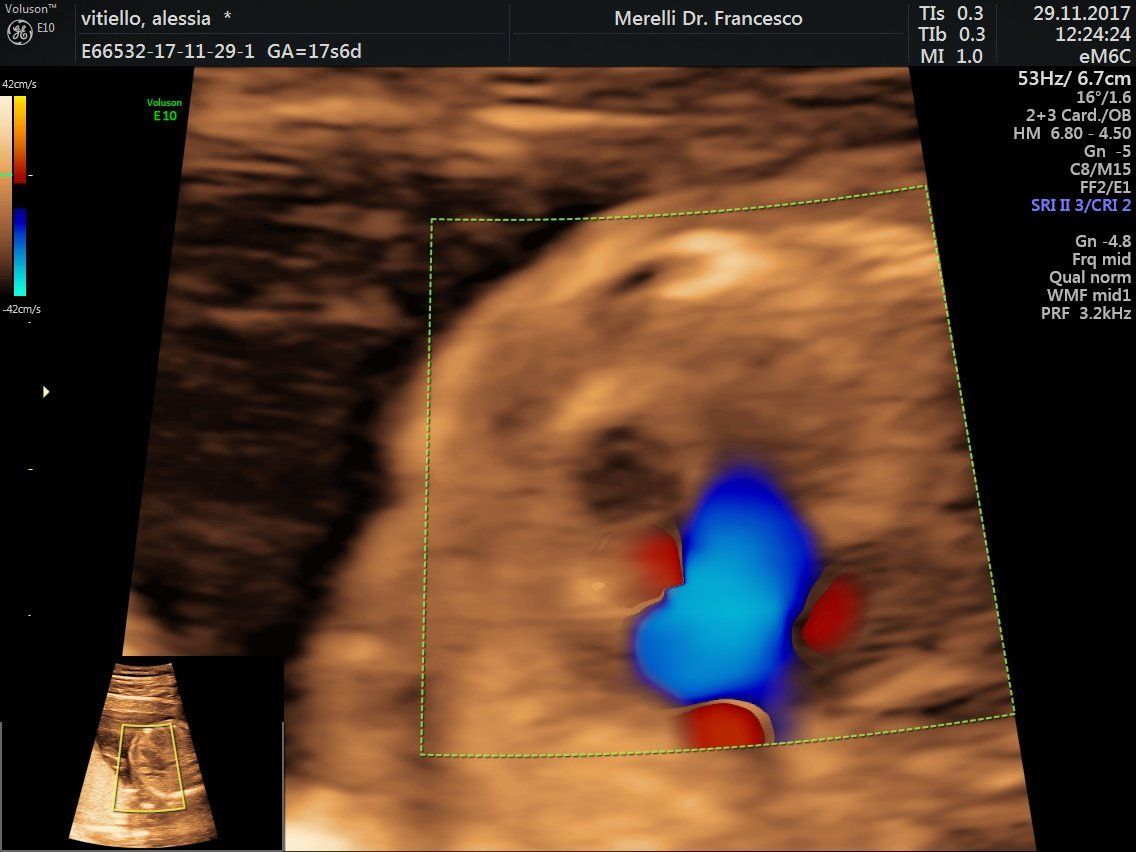

- ecografia

- ecografia pelvica

- ecografie ostetrico - ginecologiche